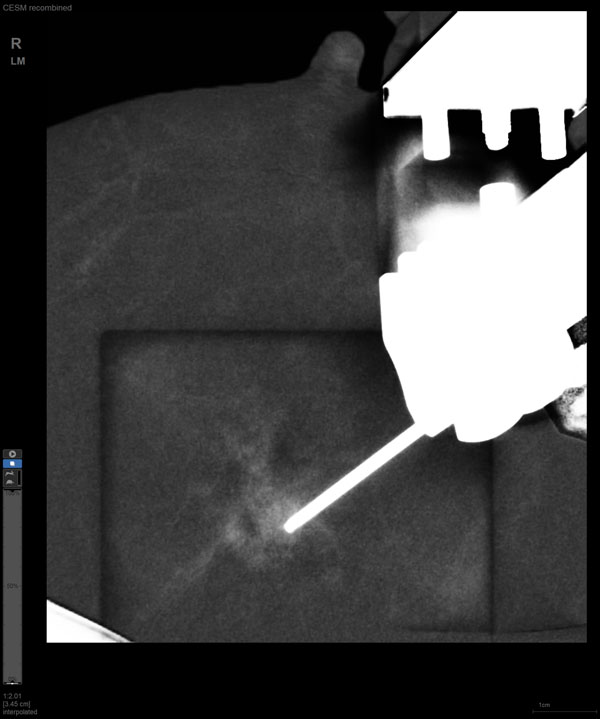

某患者增強磁共振成像MRI顯示腫瘤周邊有活性,中心區域有組織壞死。為得到準確的病理結果,穿刺靶區需避開腫物壞死區域。在與患者主管醫生充分討論后,放射科醫生為患者行CEM引導下穿刺活檢術。術中,CEM檢查腫物同樣顯示為環形強化,巧妙避開壞死區域后,穿刺靶區選擇了腫物增強早期明顯強化區域,術程順利,僅用時15分鐘。術后該患者病理結果為浸潤性導管癌Ⅱ級。

隨著計算機技術發展和乳腺X線機硬件的提升,CEM與立體定向活檢技術相結合的CEM引導下穿刺活檢術開始在臨床應用。與MRI引導的乳腺穿刺活檢相比,CEM穿刺活檢無需抗核磁耗材,成本更低,檢查速度更快。據國外研究文獻報道,CEM引導的穿刺活檢有可能成為MRI引導的乳腺穿刺活檢的有效替代方案。